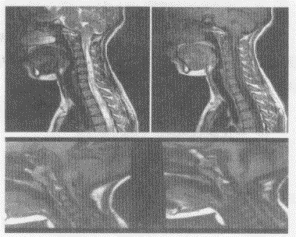

5.患者,男,30岁,两手乏力、发麻,结合图像,最可能的诊断是

正确答案:A